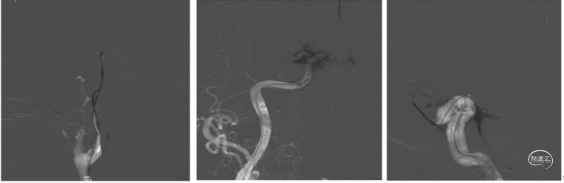

手术过程 造影见右侧颈总动脉造影未见后交通开放,未见基底动脉尖下图1。造影导管超选至右侧椎动脉造影,基底动脉中段闭塞,闭塞远端通过软膜代偿可显影,基底动脉尖显影不佳下图2、3。左侧锁骨下动脉造影见V1段、V2段严重迂曲,遂选择右侧优势椎入路。下图4、5

1、在路图下将260cm长导丝、造影导管超选至右侧椎动脉V2段。撤出造影导管,长导丝交换6F堑远端通路导管及088颅内血栓抽吸导管至V2末端。下图1

2、Transend 200mm 微导丝+Rebar 18 微导管同轴技术将6F远端通路导管及088颅内血栓抽吸导管导引至闭塞段。下图2

3.缓慢上推 088颅内血栓抽吸导管成功上至闭塞段。下图1

4.6F远端通路导管负压抽吸下撤出体外,再次使用088颅内血栓抽吸导管进行充分抽吸,取出部分血栓。下图2

行球囊穿梭辅助088到达血栓位置:

▪微导丝通过闭塞段,在闭塞远端摆动良好,判断闭塞段相对较短。

▪输送2.0×12mm颅内球囊扩张导管至闭塞段,同时轻柔推送088颅内血栓抽吸导管,顺利通过分叉部,接近闭塞段。088颅内血栓抽吸导管到达目标位置后,充分扩张球囊,缓慢完成球囊穿梭。下图1、2

撤出颅内球囊扩张导管,顺利推送088颅内血栓抽吸导管至基底动脉尖持续抽吸1分钟,保持负压抽吸回撤。下图1

回撤后见血流通畅,基底动脉尖完全再通,无明显血栓逃逸。下图2

观察15分钟以后复查造影,血流维持良好,无明显回缩,(下图3)结束手术。抽吸取出的血栓,下图4